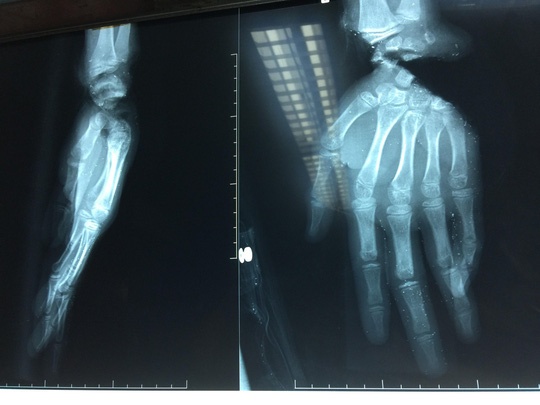

| Ảnh bàn tay suýt bị cắt lìa được chụp hình X-quang. Ảnh: Bệnh viện cung cấp |

Tuấn nhập viện trong tình trạng tái nhợt, lòng bàn tay phải bị đứt sâu, lóc da, bàn tay trái bị đứt lìa khỏi cổ tay. Khi tiếp nhận các bác sĩ đã xử trí cấp cứu các tổn thương, nối lại phần đứt lìa, gân, cơ, mạch máu, thần kinh. Sau 3 giờ 30 phút, bàn tay của Tuấn đã được cứu trước nguy cơ bị hoại tử.